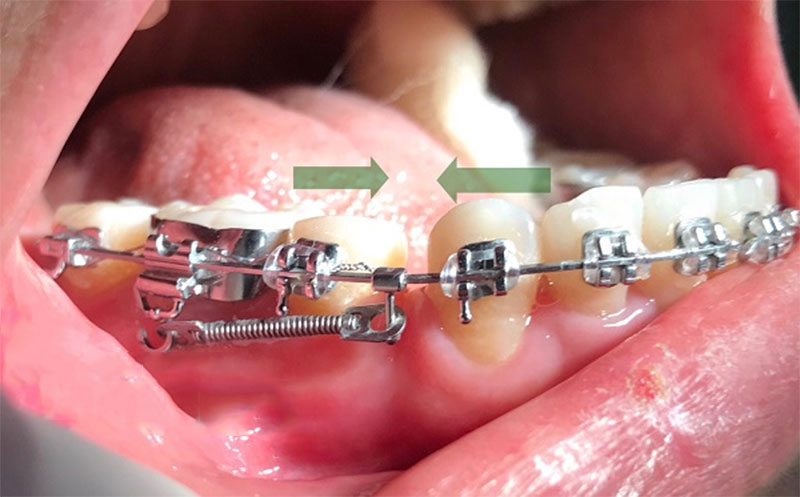

Quá trình đóng khoảng răng được thực hiện thông qua việc sử dụng lực từ các dây cung và mắc cài niềng răng. Lực này sẽ từ từ kéo các răng lại gần nhau, thu hẹp khoảng trống giữa chúng.

- Giai đoạn đóng khoảng chính: Sử dụng các dây cung và lò xo để kéo các răng lại gần nhau, thu hẹp khoảng trống.

Quá trình đóng khoảng trong niềng răng được thực hiện thông qua việc điều chỉnh các dây cung và mắc cài của niềng răng. Bác sĩ chỉnh nha sẽ thay đổi độ căng của dây cung hoặc sử dụng các phụ kiện bổ sung như lò xo để tạo lực kéo các răng lại gần nhau.